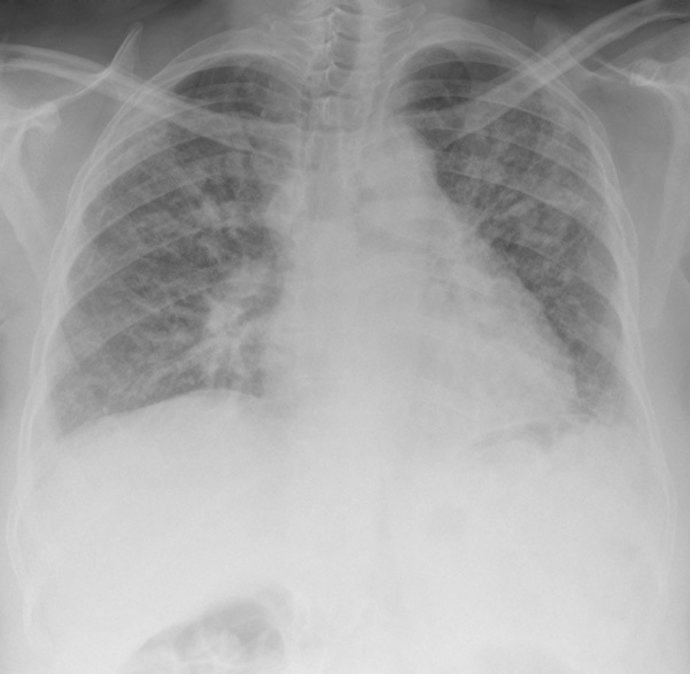

La FQ es una enfermedad genética, crónica y generalmente progresiva, de manifestación clínica diversa, con una prevalencia variable que se estima entre 1/8.000 o 1/10.000 personas y, por tanto, considerada en términos de prevalencia una Enfermedad Rara o Minoritaria según la definición de consenso aceptada para las mismas en el entorno europeo.

De todos modos, señalan que "son fundamentales" en el seguimiento las pruebas de imagen, microbiología, función pulmonar, gasometría, y cobertura antibiótica de infecciones respiratorias, soporte nutricional y digestivo, rehabilitación respiratoria, tratamiento de soporte de aclaramiento mucociliar, tratamiento de soporte domiciliario con oxigenoterapia, ventilación no invasiva. Todo ello presente en las diferentes unidades de Pediatría de los hospitales de referencia.